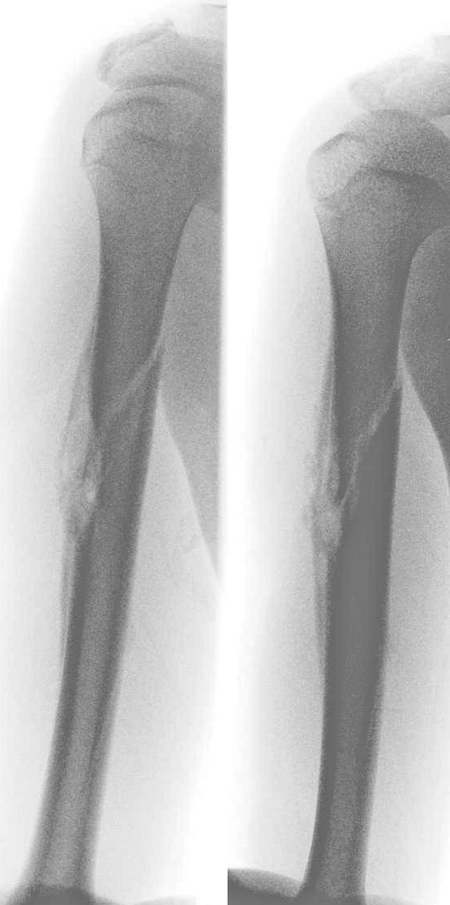

标题: X0799:右肱骨恶性骨肿瘤?,讨论!

原无外伤史,男,16y,右上臂轻微外伤 前来就诊。

肱骨骨干皮质及髓腔骨质破坏伴层状骨膜反应与线形骨折,结合病史考虑骨恶性肿瘤伴病理骨折,类型难以定论[骨肉瘤-------一般发生于干骺端],[尤文氏瘤发生骨干]

骨膜反应非常广泛,且有中断征象,皮质破坏,髓腔也有破坏,病人16岁,首先认为恶性肿瘤,(骨肉瘤吧)

肱骨隋腔密度不均匀减低,邻近皮质破坏,有明显骨膜反应,骨折为病理性的,考虑年龄仅16岁,尤文氏瘤伴病理骨折可能性大